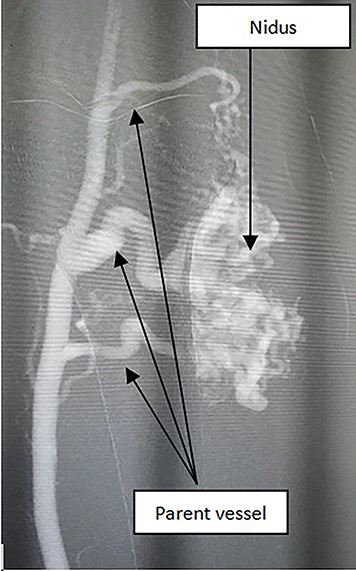

In the beginning, we recognized that this AVM has 3–4 main parent arteries (Fig. 1).

Firstly, antegrade approach at the right femoral artery was chosen with 45 cm—6 Fr—J tip guiding sheath. A microcatheter was manipulated into guiding sheath and the tip position was adjusted very close to the nidus. The guiding sheath was translated into the ostial of feeding arteries. Guiding catheter’s appearance in the ostial of the feeding branches is to reduce the distal low-limb occlusion due to liquid embolic agents when retrieving the microcatheter. Lower concentration NBCA/Lipiodol 12.5% (the ratio of the concentration is between 0.5 ml/0.5 mg NBCA and 3.5 ml Lipiodol) was aggregated. Plug and push technique was performed for injection under glue roadmap mode. Remarkably, when seeing the reflux stream very close to the tip of microcatheter which may have a risk of spreading to some normal branches of feeding artery or spreading out of the proximal part of feeding artery, the injection should be stopped and repeated 1 to 2 min later for glue concretion. When the reflux was seen at the ostial part of feeding artery, we stopped pushing NBCA/Lipiodol, pulled the microcatheter out and flushed the microcatheter with saline in preparation for another catheterization. In the case of microcatheter occlusion with unsuccessful flushing, new microcatheter will be used. These manipulations will be repeated until we positively see the disappearance of the contrast flow through the AVMs (parent vessel and nidus) under fluoroscopy.